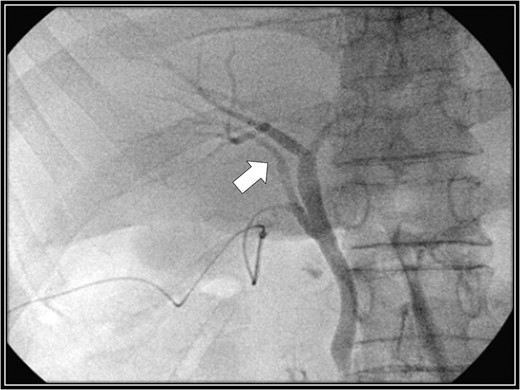

Drip-infusion cholangiography-computed tomography scan. Forty-eight days postoperatively, the right accessory hepatic duct is intact (black arrow), and it dominates an anterior segment of the right hepatic lobe, as indicated by the intraoperative cholangiography scan.

The patient was placed in supine position. Initially, intracorporeal procedures were performed in the laparoscopic view through four trocars (one 12-mm port and three 5-mm ports). We considered using intraoperative cholangiography to explore the right accessory hepatic duct. We incised the serosa by the neck of the gallbladder, used the Rouviere sulcus as a landmark, and peeled off the Calot triangle near the gallbladder. Subsequently, we identified the cystic artery and isolated it. Then we identified the cystic duct, and we inserted a cholangiography tube into it. The intraoperative cholangiography image showed that the right accessory hepatic duct branching from the cystic duct dominated an anterior segment of the right hepatic lobe (Fig. 3). Next, we isolated the cystic duct while preserving the right accessory hepatic duct. We resected the gallbladder. The total operating time was 125 min, and the intraoperative blood loss was minimal. Since the patient's postoperative course was uneventful, he was discharged 4 days later. We performed drip-infusion cholangiography-CT (DIC-CT) 48 days postoperatively. The DIC-CT scan demonstrated that the right accessory hepatic duct was intact, and it dominated an anterior segment of the right hepatic lobe (Fig. 4).